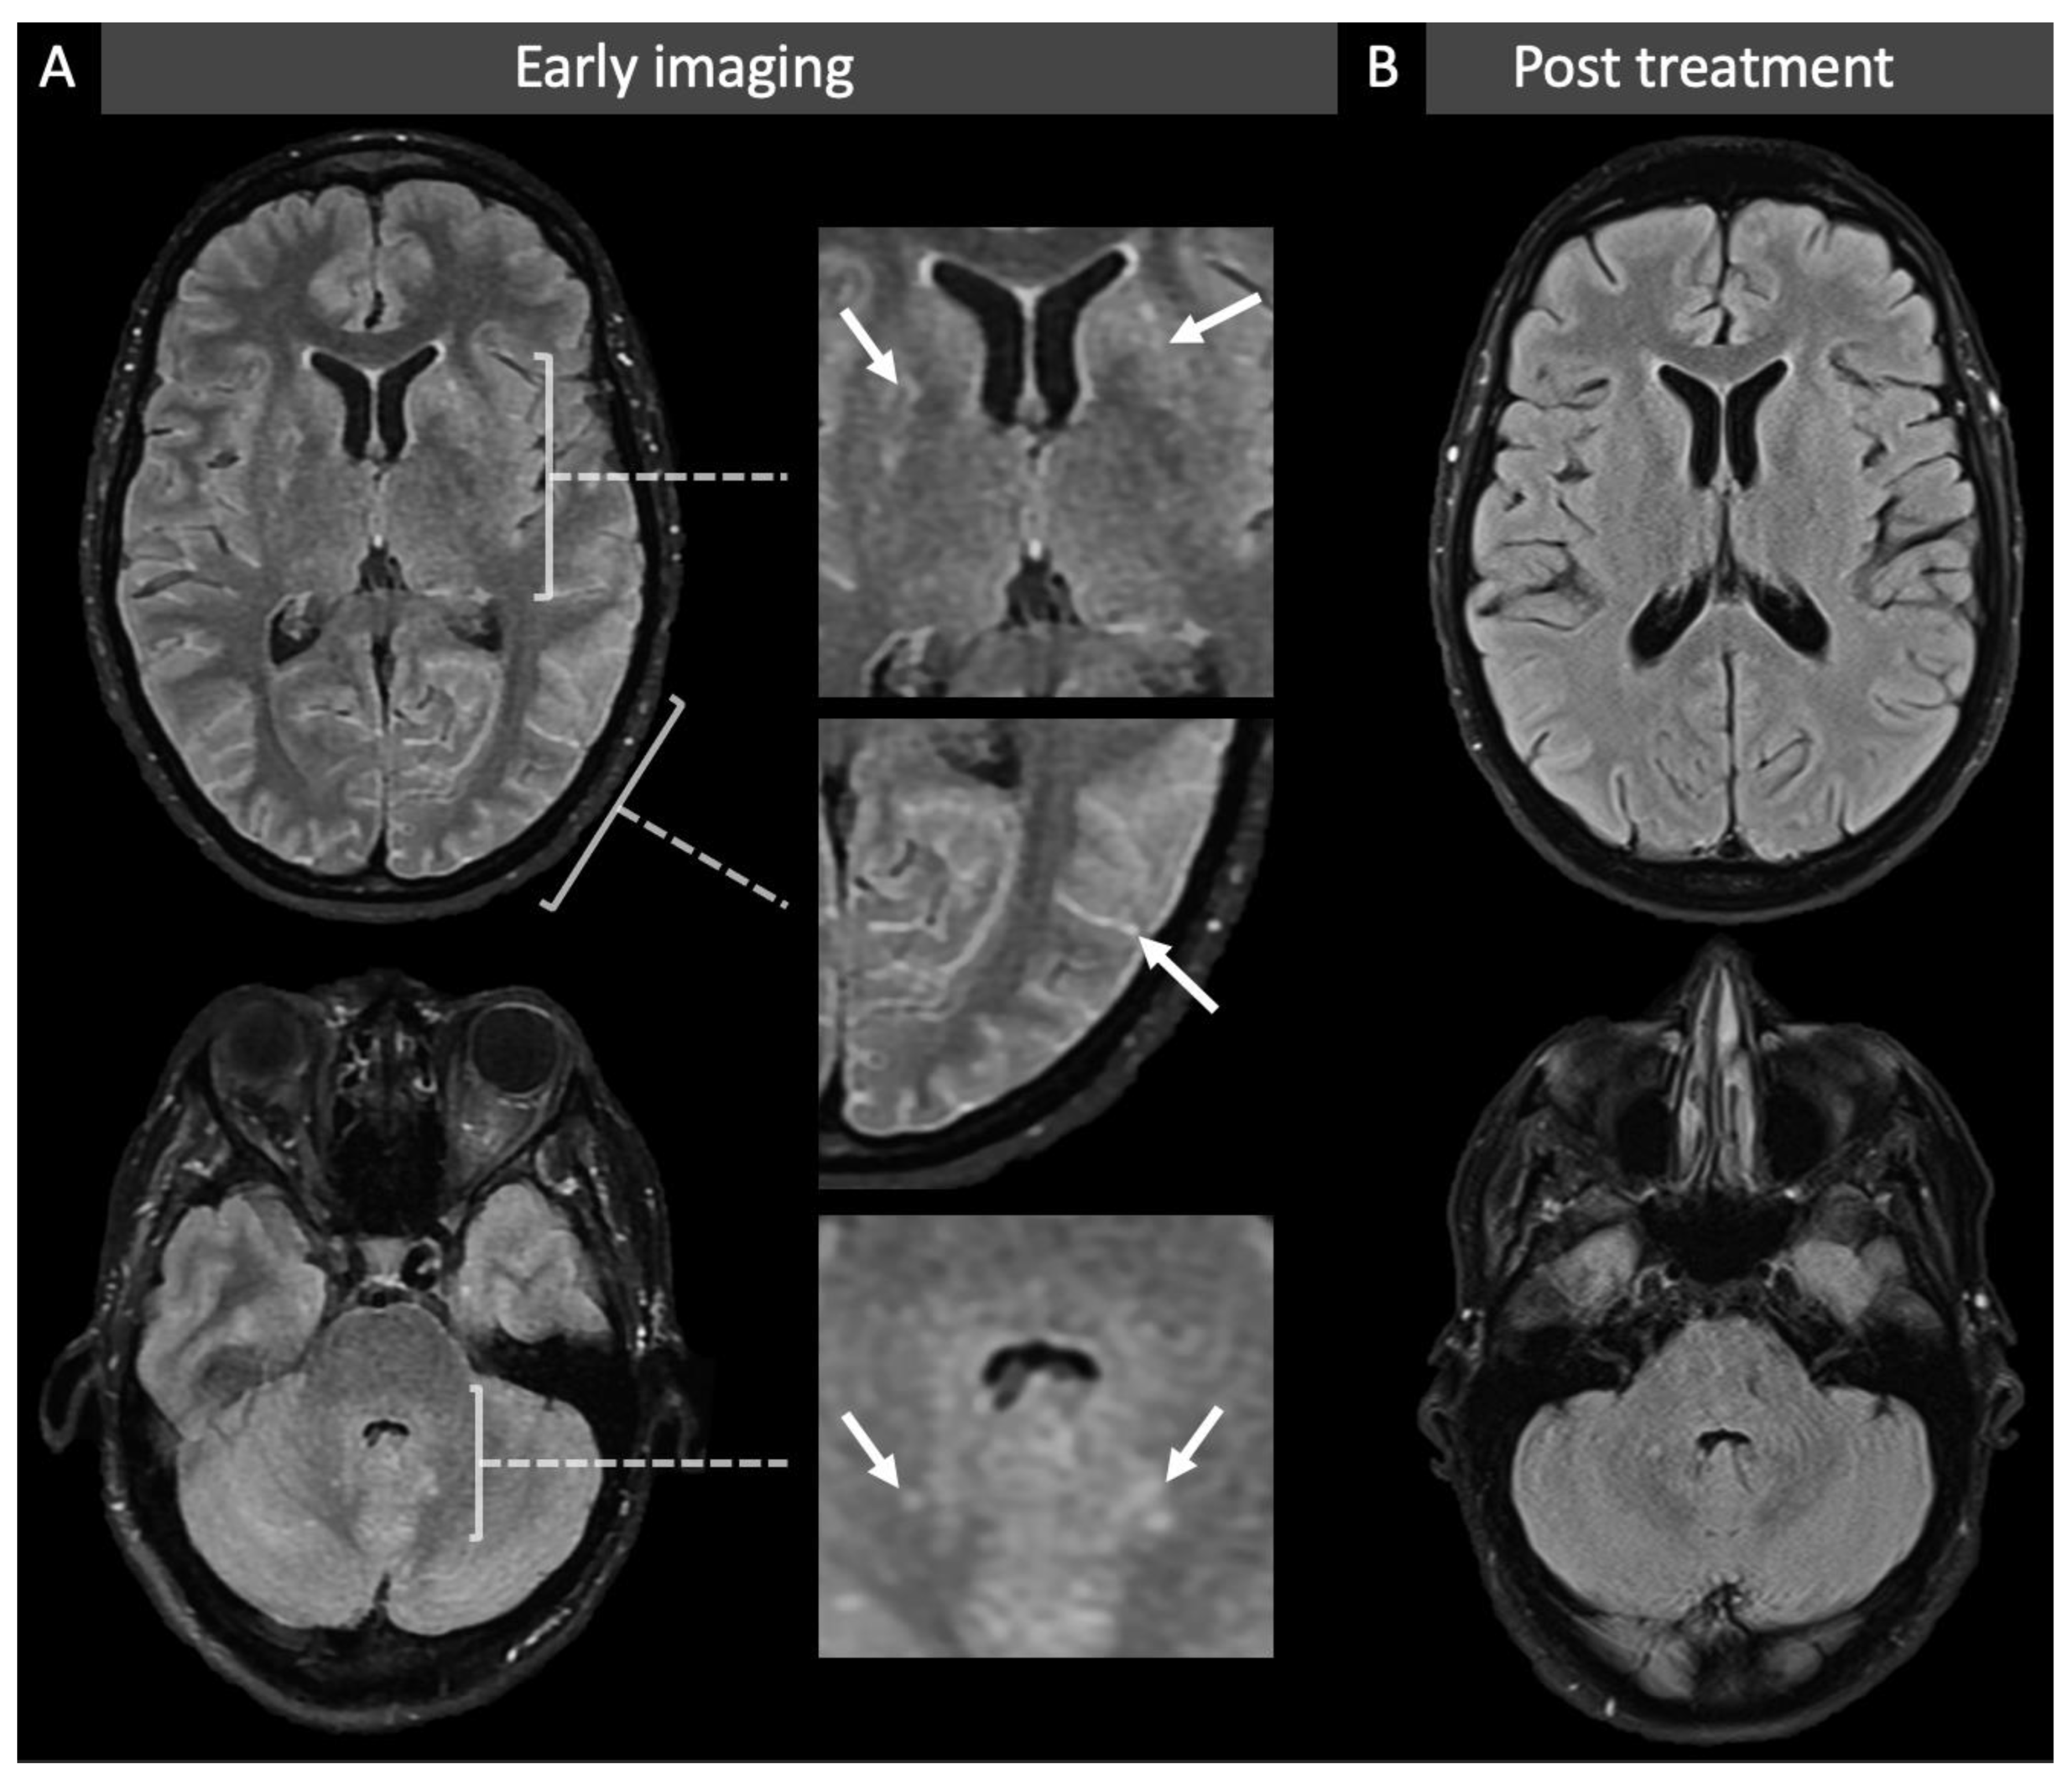

2. Case Presentation